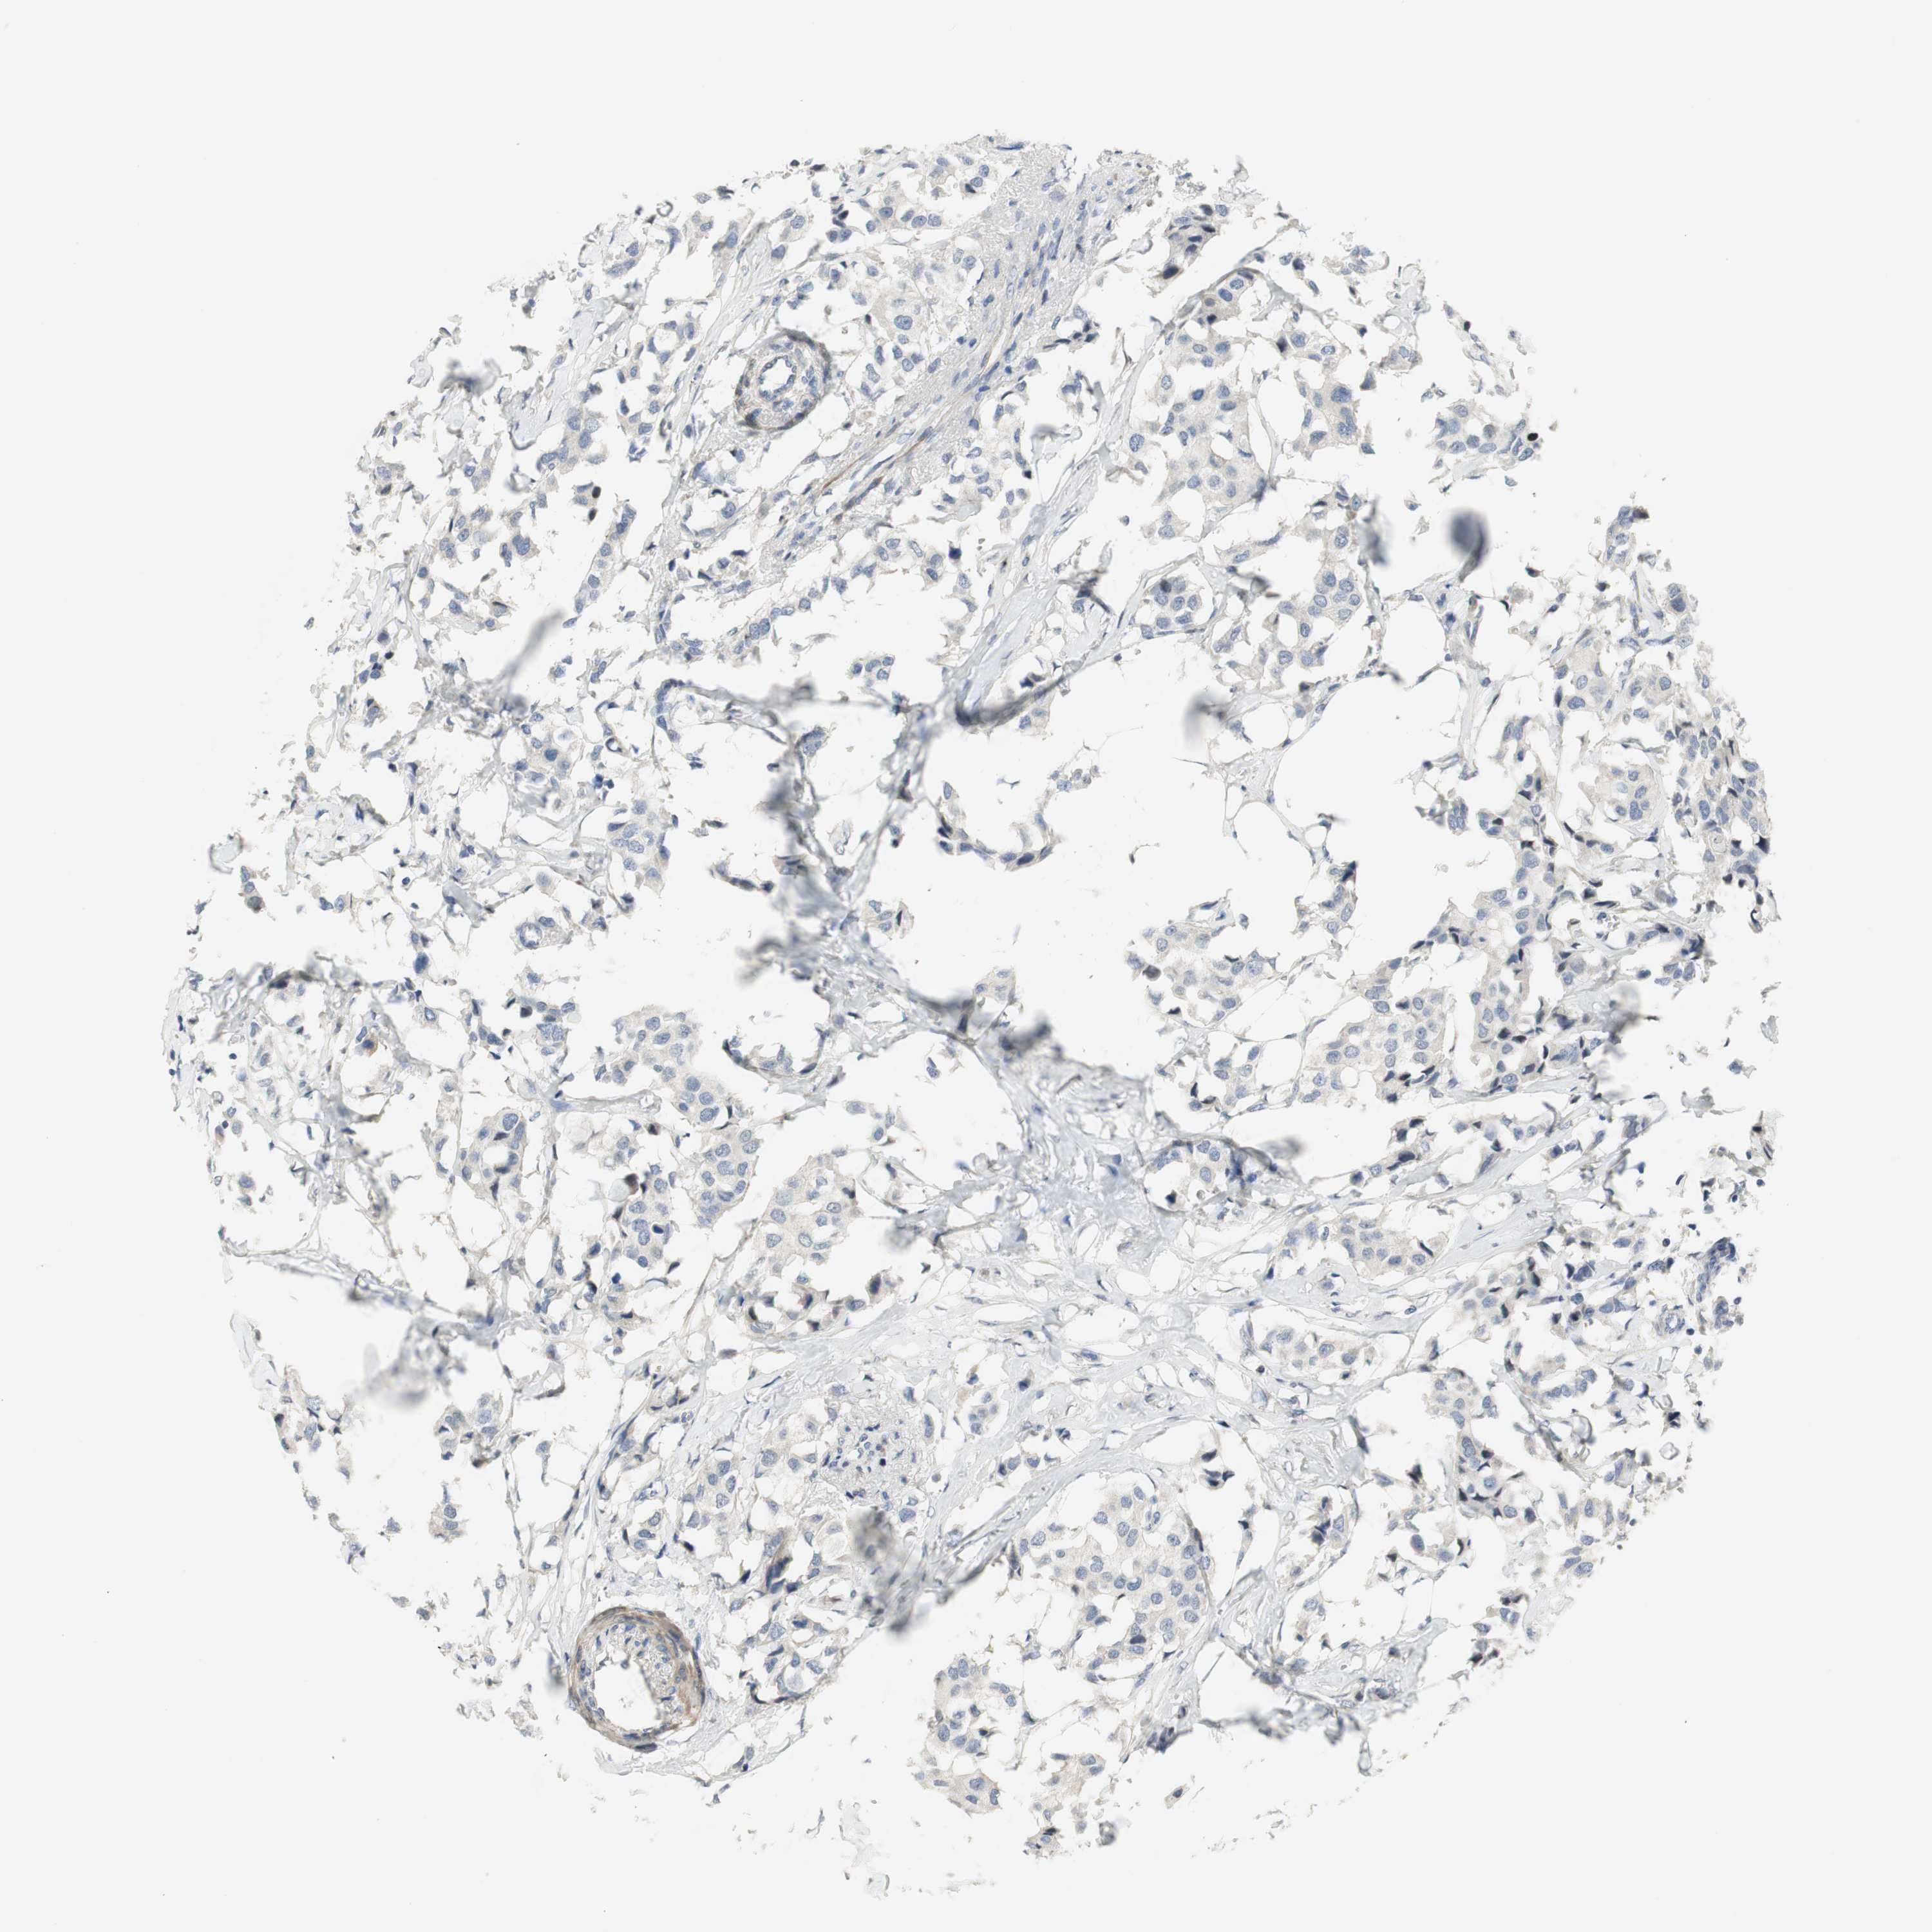

CANCER BREAST CANCER Show tissue menu

BRCA TCGA BRCA VALIDATION PROTEIN EXPRESSION